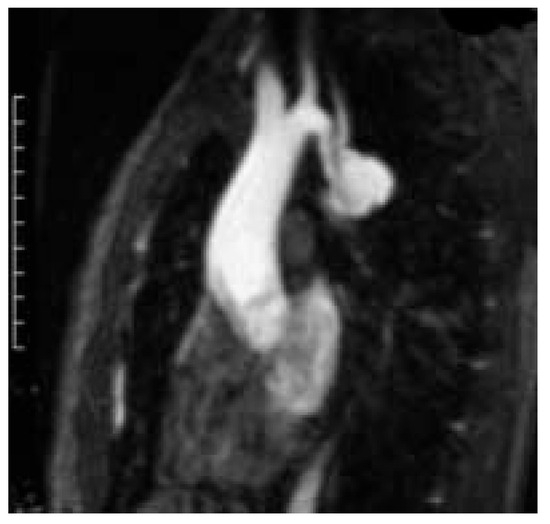

Une patiente de 31 ans souffrant d’une cardiopathie congénitale consulte car elle souhaite une grossesse [...]